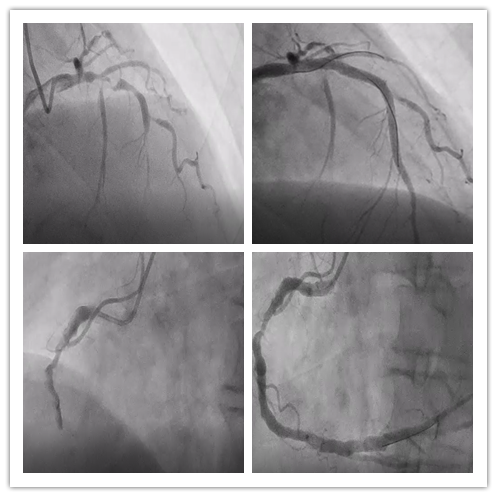

术前术后造影结果

钱嗲嗲到达急诊抢救室后,仅用了2分钟就完成了心电图检查,心电图提示为急性下壁心肌梗死,胸痛中心立即启动了绿色通道,迅速将钱嗲嗲送往介入手术室,完成急诊冠脉造影检查,造影发现三支冠脉血管已经闭塞了二支,情况十分危急,随时有发生猝死的可能。

刚下台的张宇副主任医师还没来得急脱下重重的铅衣,便再次上台,在主动脉球囊反搏的支持下仅用半小时便成功开通了二支闭塞的冠状动脉血管并植入了药物支架,钱嗲嗲立马感觉胸痛症状明显缓解,顺利结束手术后转运至CCU继续治疗。